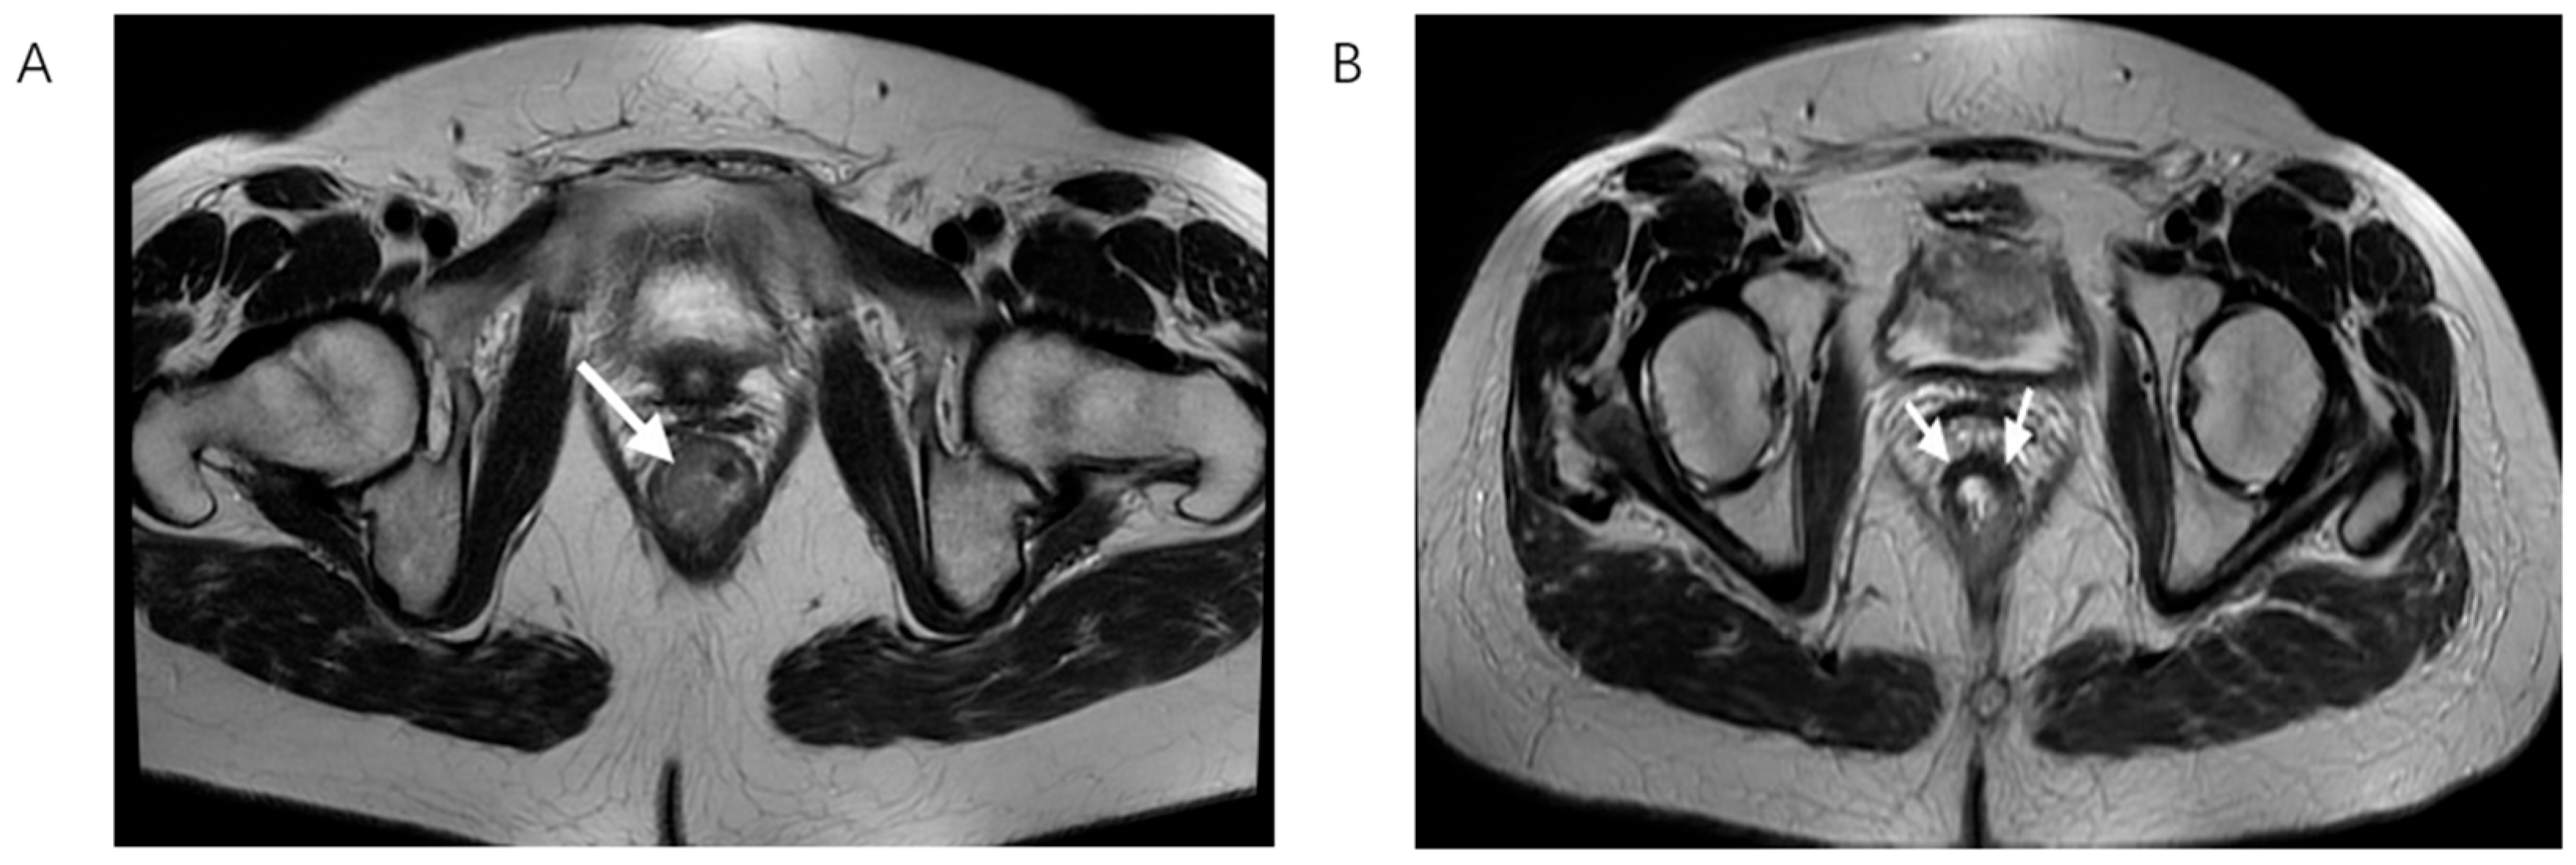

In accordance with widely recommended rectal cancer protocols, initial MRI is performed two weeks after histopathological verification while post-treatment MRI scan was completed 6 to 8 after the completion of chemoradiotherapy as it is shown that this time frame is needed for full effect of the radiation therapy as well as for potential side effects including edema and inflammation to improve significantly (Figure 2) [9,20].

Figure 2.

T2-weighted MRI scan in the axial plane showing rectal cancer before (A) and after nCRT (B), white arrows showing tumor bed. On the left, there is the lesion with its typical intermediate signal intensity, while on the right, a drop in the signal intensity is shown, caused by therapy-induced fibrosis.